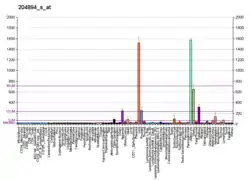

Amine oxidase, copper containing 3 (AOC3), also known as vascular adhesion protein (VAP-1) and HPAO is an enzyme that in humans is encoded by the AOC3 gene on chromosome 17. This protein is a member of the semicarbazide-sensitive amine oxidase (SSAO; aka primary amine oxidase) family of enzymes and is associated with many vascular diseases.[5]

VAP-1 is a type 1 membrane-bound glycoprotein that has a distal adhesion domain and an enzymatically active amine oxidase site outside of the membrane.[6][7] The AOC3 gene is mapped onto 17q21 and has an exon count of 6.[5]

Amine oxidases are a family of enzymes that catalyze the oxidation of various endogenous amines, including histamine or dopamine. VAP-1 constitutes the copper dependent class of amine oxidases, such as lysyl oxidase or lysine demethylase, and is one of the four known in humans. The other class is flavin dependent such as monoamine oxidase (MAO) A and B.[5][8] VAP-1, in particular, catalyzes the oxidative conversion of primary amines (methylamine and aminoacetone) to aldehydes (formaldehyde and methylglyoxal) ammonium and hydrogen peroxide in the presence of copper and quinone cofactor.[8][9][10]